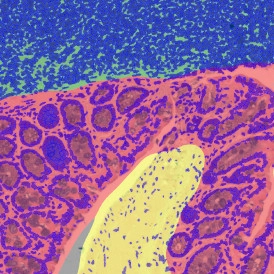

The IHC Small Intestine - Dots App provides nuclei segmentation and detection of tissue and villi based on nuclei staining (crypts need to be defined manually). Furthermore, it allows dot detection for one dot markers (CISH, RNAScope, SISH) within villi and crypt areas. Dot parameters are provided for villi and crypts and for dots and include count, mean intensity, total dot area, the sum of intensity.

App Category 2